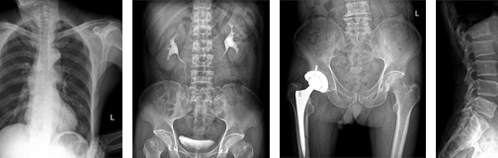

UC臂直接數(shù)字化X光機可以垂直、水平運動和轉(zhuǎn)動,智能化設(shè)計,滿足人體所有部位多角度攝影。

4. 探測器可旋轉(zhuǎn),能夠滿足人體所有部位(如:下顎、跟骨軸等)多角度攝片要求。

5.17×17英寸成像面積,完全滿足臨床檢查需要。